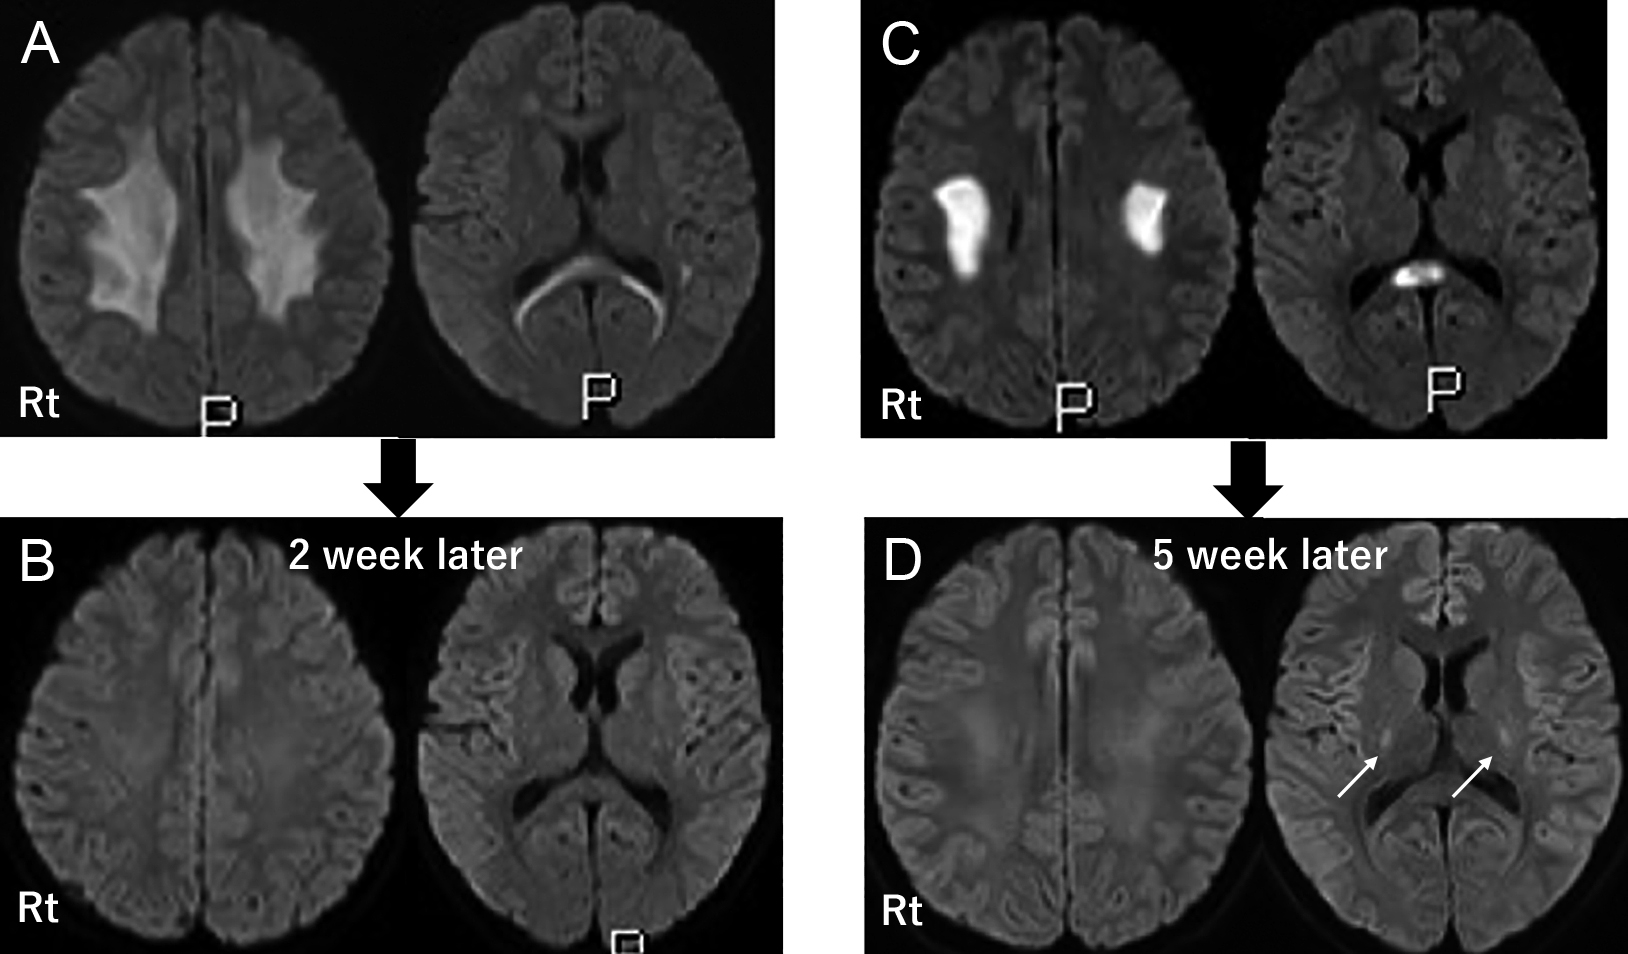

A case of X-linked Charcot–Marie–Tooth disease type 1 (CMTX1) diagnosed based on recurrent brain lesions despite peripheral neuropathy responsive to immunotherapy